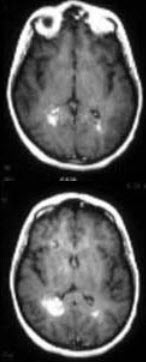

男性,40岁,因感冒半月后出现性情改变如欣快、暴躁和猜疑,以及EEG弥漫性慢波,以脑炎诊断住院20天,经治疗病情明显好转,准备3日后出院。但患者病情反复,MRI如图,应考虑( )

A:球后视神经炎

B:重症肌无力

C:多发性硬化

D:脑干肿瘤

E:脊髓压迫症